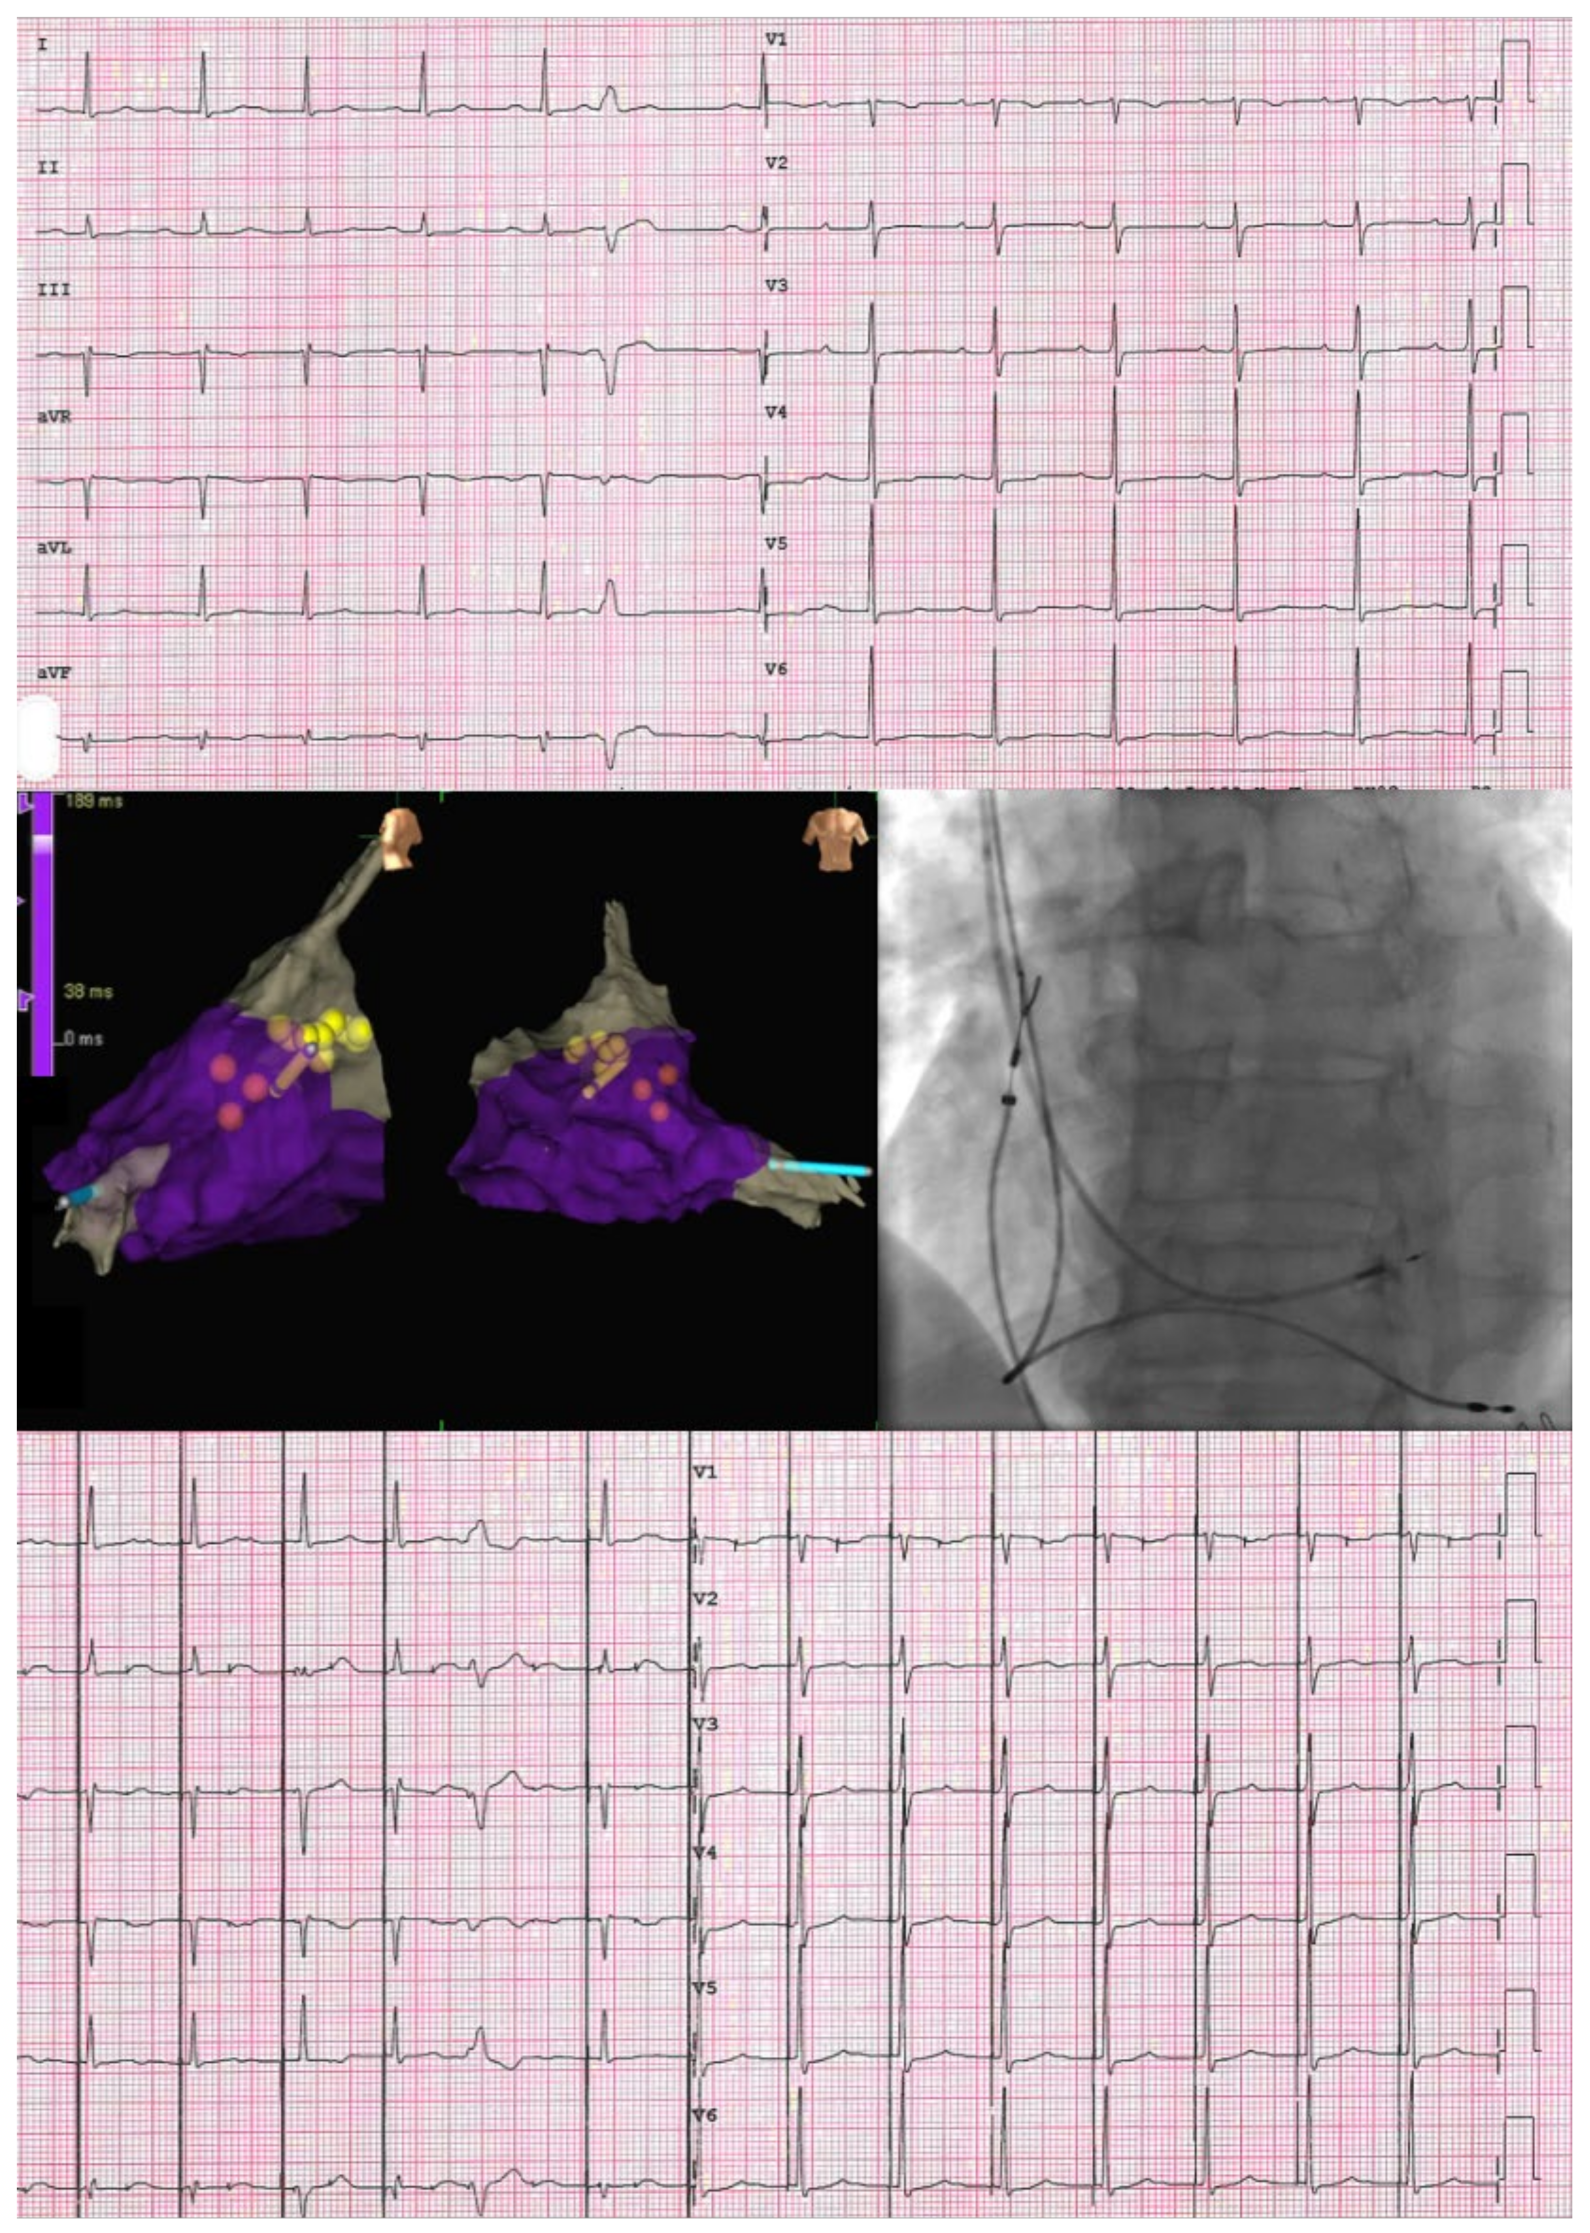

ECG and SVA Myocardial Work